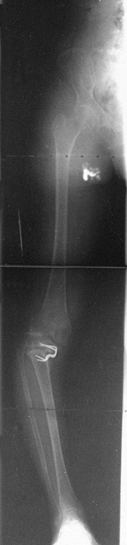

![]() |

Figure 32.16.

A high tibial osteotomy was performed to correct a valgus deformity of the distal femur. In addition to the sloped joint orientation that was present preoperatively, the patient is now developing collapse into varus and lateral subluxation. This illustrates why a normal tibia should not be osteotomized to correct for a deformity in the distal femur. |